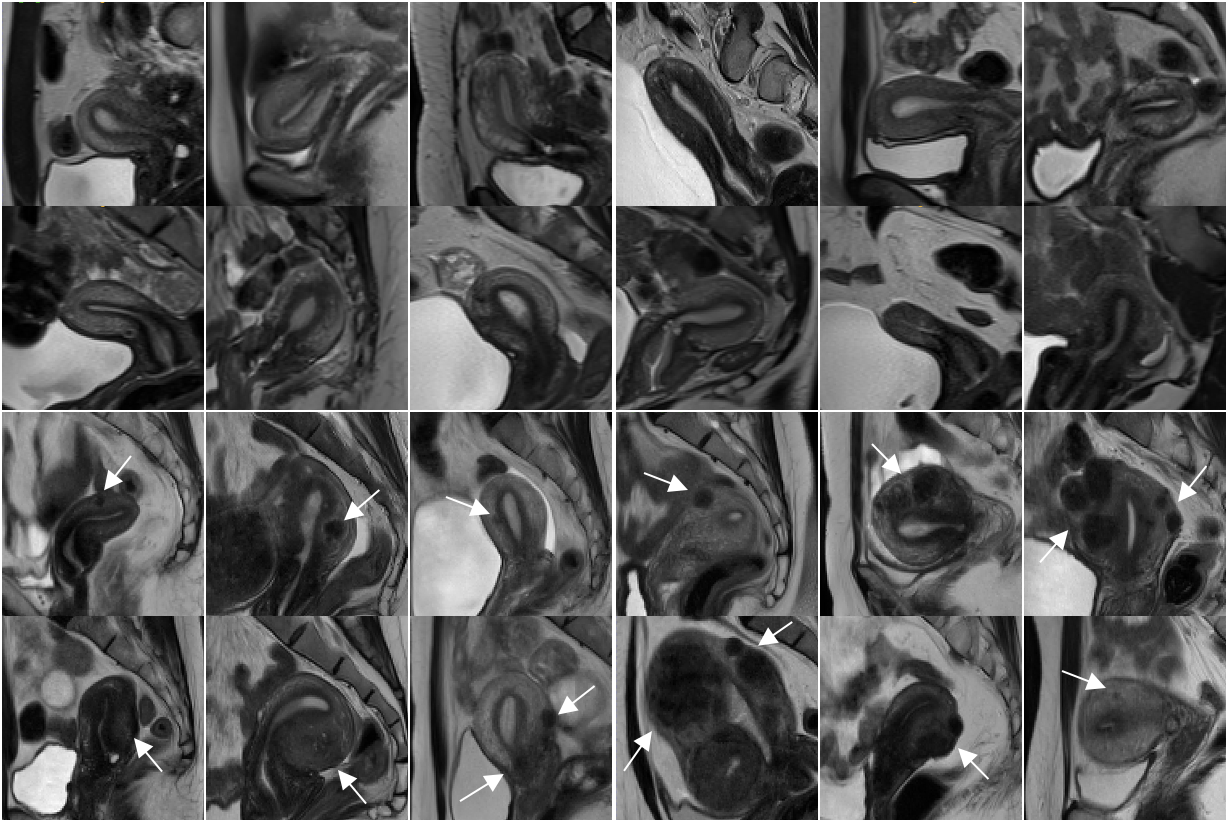

Pelvic diseases pose a significant health challenge for women of reproductive age, affecting approximately of this population [24] and contributing to of the global disease burden [45]. These conditions include uterine myomas, adenomyosis, endometriosis, ovarian tumors, and endometrial or cervical cancer, among others — each presenting unique diagnostic challenges due to their variable appearance in medical imaging [47]. This variability often results in diagnostic delays, misclassification, unnecessary suffering, and, in some cases, avoidable surgical interventions. For example, endometriosis affects about of women, yet is often misdiagnosed, with an average delay of eight years and nearly of patients initially misdiagnosed [28, 13]. An important factor contributing to the complexity of pelvic disease diagnosis is the substantial anatomical variability of the uterus. While the anteverted and anteflexed positions are most common in healthy uteri, other orientations, such as retroverted, retroflexed, or intermediate, represent normal variants [47] (see Fig. 1).

4.1 Data Set

The data sets exhibit substantial anatomical and technical imbalances. Uterine positioning is heavily skewed toward anteflexed (AF) configurations across all data sets: in the training set ( anteverted (AV), retroverted (RV)), in DUnhealthy(UMD) ( AV, RV), and in the in-house subset. Retroflexed (RF) cases are markedly underrepresented, with only scans in training data ( AV, RV), in DUnhealthy(UMD) ( AV, RV), and in the in-house subset ( AV, RV). Field-strength distributions are similarly imbalanced. While DHealthy comprises high-field scans (alongside at and at ), DUnhealthy(UMD) was acquired exclusively at . The in-house subset exhibits a different pattern with predominantly lower field strengths (, , and scans at , , and , respectively).

Random samples from DHealthy_Gen demonstrate substantial variability in the generated data. As depicted in Fig. 5, the AV, AF uteri position is most frequently synthesized, while RV, AF (blue borders) and RV, RF (green borders) uteri are also represented. The absence of AV, RF position reflects the corresponding imbalance in the real training data (Sec. 4.1).

The generated images further capture both anatomical and acquisition-related variability. Orange borders indicate simulated artifacts, and the red arrow denotes the presence of Nabothian cysts. The samples exhibit diverse contrast profiles, including low uterine–background contrast and markedly higher contrast with reduced uterine signal intensity. Variations in myometrial signal intensity are also observed, as well as differences in uterine size, with one example (last row, second from right) demonstrating a markedly enlarged uterus, highlighting the diversity represented by the synthetic data.